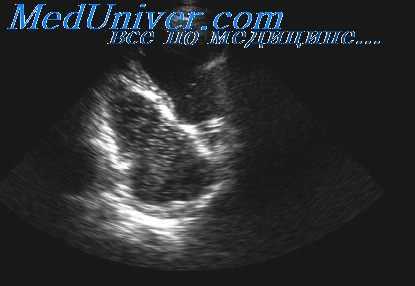

Оценка нерастворенной циркулирующей в крови газообразной фазы в виде эмболов и обследование камер сердца и нижней полой вены после декомпрессии с помощью систем двухмерно-пространственного ультразвукового сканирования является; достаточно эффективной. Ручной фазовосмещающий датчик-преобразователь располагают у левой границы грудины между четвертым и пятым межреберьем в положении обследуемого лежа. Затем с целью ориентировки преобразователь перемещают, чтобы получить изображение по длинной оси левого желудочка (ЛЖ).

Несколько иной ракурс можно получить, расположив преобразователь вблизи верхушки сердца и производя сканирование вверх по направлению к предсердиям. Вдоль этого направления может быть получен так называемый «вид четырех камер». В этом случае можно увидеть. как оба желудочка, так и оба предсердия. Такой ракурс особенно удобен для выявления артериальных газообразных эмболов.

Для качественного сравнения циркулирующих в крови газовых пузырьков оказалась приемлемой описанная ниже шкала степени обнаружения пузырьков методом двухмерно-пространственного сканирования, сходная со шкалой для доплеровского метода.

На снимке а показаны четыре камеры сердца: ПП, ПЖ, ЛП и левый желудочек (ЛЖ). На представленном снимке, сделанном во время диастолы, видны также межжелудочковая перегородка и передняя створка митрального клапана. Здесь имеет место II степень обнаружения газовых пузырьков, причем последние видны как белые пятнышки в просвете ПЖ. Венозные газовые пузырьки обозначены как ВП. Заметьте, что ЛП и ЛЖ свободны от газовых пузырьков. В конце диастолы (снимок б) артериальный газовый пузырек (АП) появляется в ЛЖ.